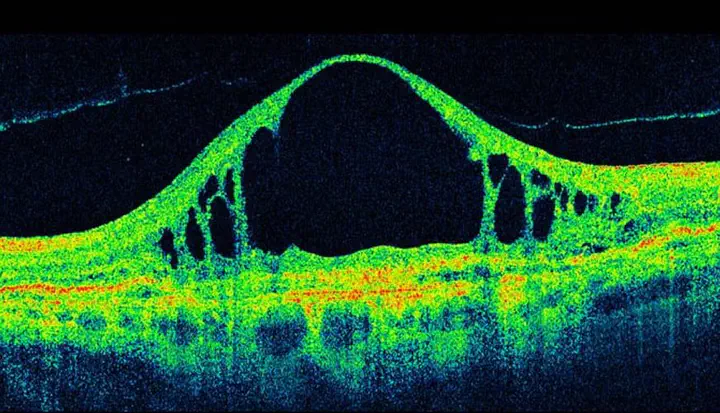

Biomedical image classification for diseases is a lengthy and manual process. However, recent progress in computer vision has enabled detection and classification of medical images using machine intelligence a more feasible solution. We explore the possibility of automated detection and classification of retinal abnormlaities from retinal OCT scan images of ptients. We develop an algorithm to detect the region of interest from a retinal OCT scan and use a computationally inexpensive signle layer convolutional neural network structure for the classification process. Our model is trained on an open sourece retinal OCT dataset containing 83,484 images of various tunnel disease patients and provides a feasible classification accuracy.